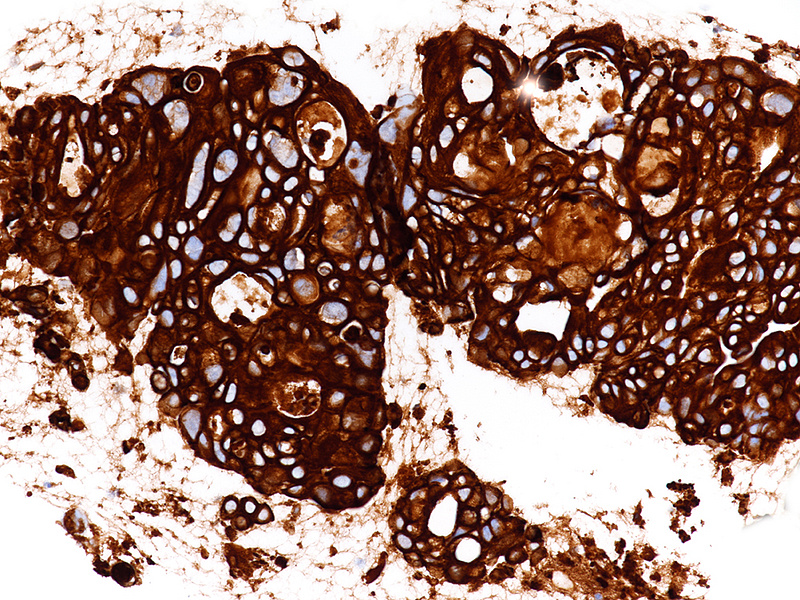

The well-sampled biopsy showed fragments of a necrotising carcinoma, arranged in isolated cells, small aggregates of cells and poorly formed glandular structures (Panels A-B). The tumour cells demonstrated abundant eosinophilic cytoplasm and severely pleomorphic, hyperchromatic nuclei with distinct nucleoli. Brisk mitotic activity was noted (Panel C). Within some clusters, the neoplastic cells had a more polygonal appearance, with intercellular desmosomes, more basophilic cytoplasm and evidence of dyskeratosis (Panels D-E).

By immunohistochemistry, the tumour cells were strongly and diffusely positive for CK7 (Panel F), focally positive also for p40 (Panel G) and CK20 (not shown). Ki67 labelling index confirmed the suspected high proliferation rate, estimated between 40-50% (Panel H). The immunohistochemical screening for DNA mismatch repair (MMR) deficiency showed no loss of protein expression. A final diagnosis of poorly (to undifferentiated) adenocarcinoma of the pancreas with squamous differentiation (consistent with adenosquamous carcinoma) was made.